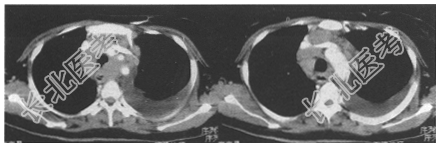

- [材料题] 患者,男。咳嗽、咳痰6个月余,胸痛、乏力1个月。查体:左下肺呼吸音无。X线平片示:上纵隔影增宽,左侧中量胸腔积液。胸部CT如下图所示。

- 简答题1、该病例最可能的诊断是什么?

- 简答题2、该病例常见的CT表现是什么?

- 简答题3、该病例最好的治疗方法是什么?